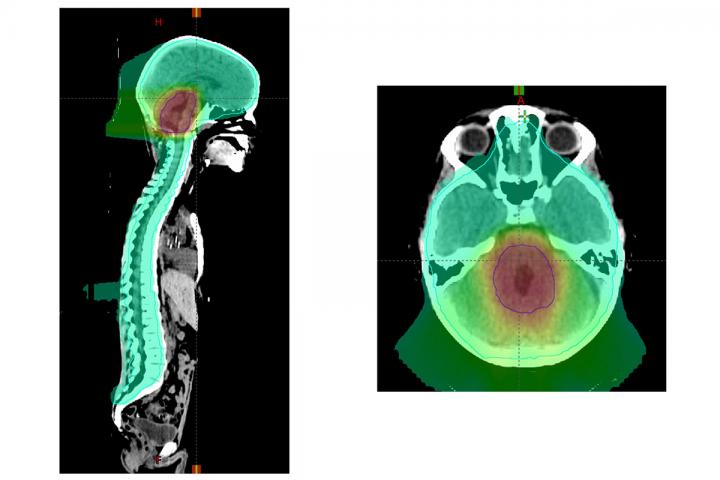

image: A new study led by Washington University School of Medicine in St. Louis provides new guidance on the treatment of medulloblastoma, a pediatric brain cancer. Some aspects of radiation therapy may be reduced while still providing effective treatment. Shown is a proton therapy plan for a patient with medulloblastoma. An extra "boost" radiation dose to the back of the brain is shown in red. The preventive radiation treatment to the entire brain and spine is shown in green.

Medulloblastoma is a rare but devastating childhood brain cancer. This cancer can spread through the spinal fluid and be deposited elsewhere in the brain or spine. Radiation therapy to the whole brain and spine followed by an extra radiation dose to the back of the brain prevents this spread and has been the standard of care. However, the radiation used to treat such tumors takes a toll on the brain, damaging cognitive function, especially in younger patients whose brains are just beginning to develop.

A national study led by Washington University School of Medicine in St. Louis and St. Jude Children's Research Hospital suggests that children with what is called "average risk medulloblastoma" can receive a radiation "boost" to a smaller volume of the brain at the end of a six-week course of radiation treatment and still maintain the same disease control as those receiving radiation to a larger area. But the researchers also found that the dose of the preventive radiation treatments given to the whole brain and spine over the six-week regimen cannot be reduced without reducing survival. Further, the researchers showed that patients' cancers responded differently to therapy depending on the biology of the tumors, setting the stage for future clinical trials of more targeted treatments.

Collaborating with children's hospitals across the U.S. and internationally, the researchers evaluated 464 patients treated for average risk medulloblastoma that was diagnosed between ages 3 and 21. Younger patients, ages 3 to 7 -- a key time for brain development -- were randomly assigned to receive either standard dose (23.4 gray) or low dose (18 gray) radiation to the head and spine region in each of 30 treatments given over six weeks. Older patients all received the standard dose, since their brain development is less vulnerable to radiation. In addition, all patients were randomly assigned to receive two different sizes of a radiation "boost" at the end of the six weeks of therapy. For the boost, all patients received a cumulative radiation dose of 54 gray to either the entire region of the brain called the posterior fossa, which includes the cerebellum, or to a smaller region of the brain that includes the original outline of the tumor plus an additional margin of up to about two centimeters beyond the original tumor boundary.